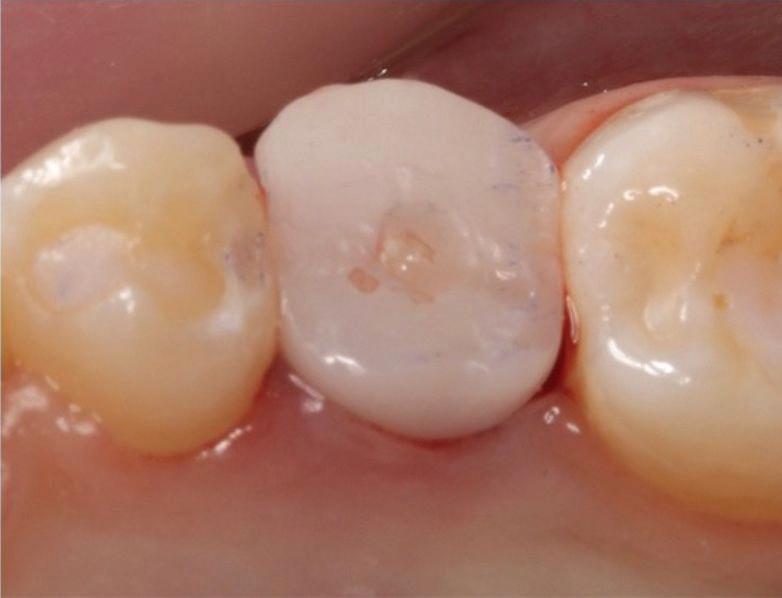

Estelite Asteria (Tokuyama)One of my favourite composite resin materials is Asteria which is a light-cured radiopaque composite for universal use. It considerably simplifies multilayer techniques yet delivers outstanding aesthetics with excellent polishability. Unlike mul tilayer techniques used with conventional composites, Asteria uses only 2 layers for optimal results without compromising aesthetics. The microstructure of the material produces a light diffusion that helps blend in with the natural tooth structure. The chameleon like nature of the material allows a blending of the materials to natural tooth structure and it allows excellent polishability which retains its lustre over time.